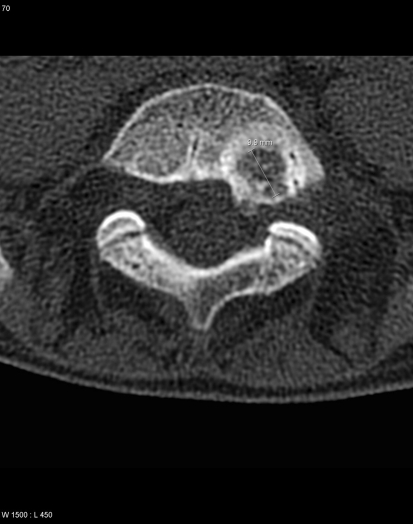

Fig. 1.

Computed tomographic image of the osteoid osteoma located in L5 in patient 5, which required a double-angulated approach